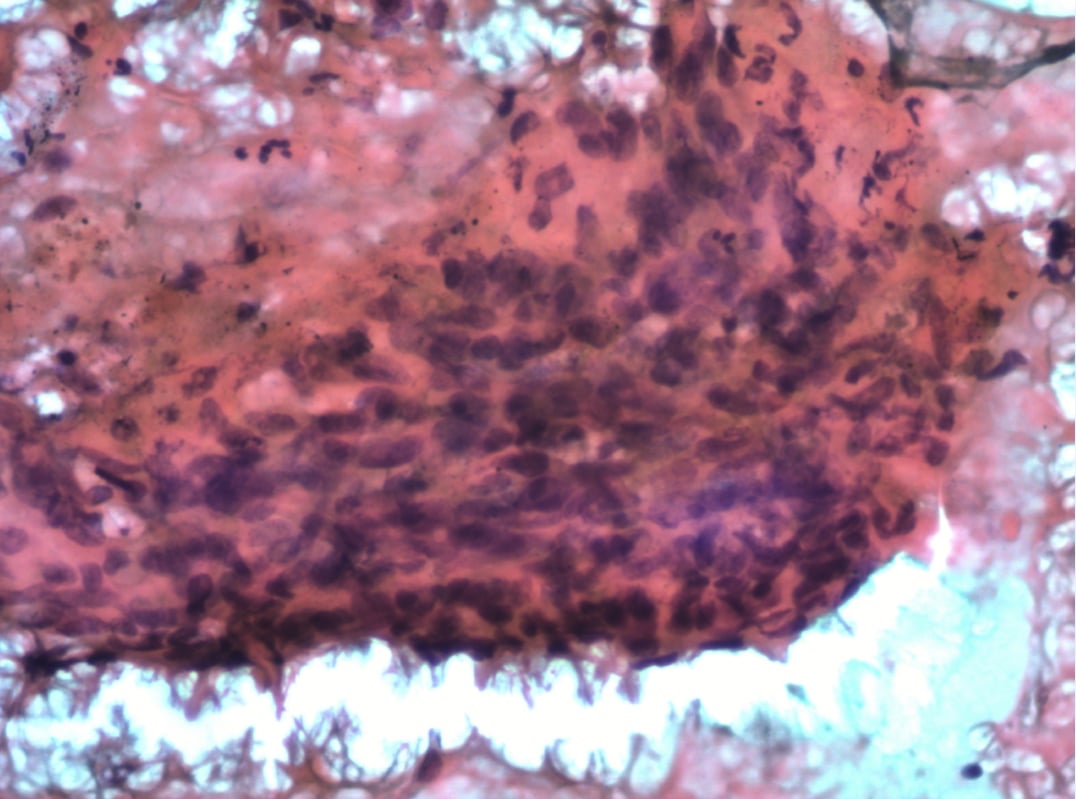

2. 组织病理活检与镜下观:

穿刺组织大体观为灰白组织一堆,约3×2×1mm。镜下观显示肿瘤细胞弥漫分布呈片状,部分区域可见较多出血。高倍镜下,肿瘤细胞呈梭形、多边形或卵圆形,具有显著异型性,胞界不清,细胞核呈梭形或卵圆形,可见小核仁。胞质嗜碱性,少许呈空泡状,病理性核分裂像易见,局灶可见坏死。部分区域似有形成血管腔的趋势,腔内可见红细胞。

图4 组织学检查:低倍镜下见肿瘤弥漫分布呈片状。

图5 组织学检查:高倍镜下见肿瘤细胞呈梭形、多边形或卵圆形,细胞具有异型性。

图6 高倍镜下局灶见坏死;部分区域似有形成血管腔的趋势。